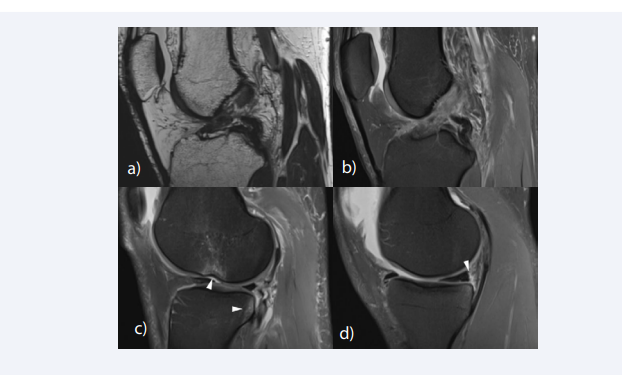

MR findings of ACL injury can be divided into primary signs related to the changes of the ACL itself, and secondary signs related to changes in the surrounding structures. The most reliable primary sign of acute ACL tear is the discontinuity of the ligament fibers, and the failure of the ACL fascicles to parallel the Blumensaat line on sagittal image [54] (Figure 2A).

Primary and secondary signs of ACL tear. (A) Sagittal T2-weighted image shows discontinuity of the ACL at the mid-substance indicating a complete tear. (B)  Sagittal fat-suppressed proton density-weighted shows diffuse enlargement and cloud-like hyperintense signal intensity of the ligament, resulting from edema and  hemorrhagic change of the ligament. (c) Sagittal image through the lateral compartment shows kissing bone contusion involving the posterior aspect of the lateral  tibial plateau and the mid portion of the lateral femoral condyle at the sulcus terminalis, which indicates a pivot shift injury. A slight depression fracture at the sulcus  terminalis of the lateral femoral condyle is noted (“deep notch sign”) (D) A thin fluid signal is interposed between the posterior horn of the medial meniscus and the  posteromedial capsule, leading to the diagnosis of meniscal ramp lesion associated with ACL tear.

Figure 2: Primary and secondary signs of ACL tear. (A) Sagittal T2-weighted image shows discontinuity of the ACL at the mid-substance indicating a complete tear. (B) Sagittal fat-suppressed proton density-weighted shows diffuse enlargement and cloud-like hyperintense signal intensity of the ligament, resulting from edema and hemorrhagic change of the ligament. (c) Sagittal image through the lateral compartment shows kissing bone contusion involving the posterior aspect of the lateral tibial plateau and the mid portion of the lateral femoral condyle at the sulcus terminalis, which indicates a pivot shift injury. A slight depression fracture at the sulcus terminalis of the lateral femoral condyle is noted (“deep notch sign”) (D) A thin fluid signal is interposed between the posterior horn of the medial meniscus and the posteromedial capsule, leading to the diagnosis of meniscal ramp lesion associated with ACL tear.

The ligament fibers may be edematous and hemorrhagic resulting in diffuse enlargement and cloud-like hyperintense T2 signal in the acute to subacute phase [55] (Figure 2B). The proximal stump of the torn ACL is usually oriented more vertically, and the distal stump more horizontally compared with the Blumensaat line. Nonvisualization of the ACL fibers is a common and specific finding of chronic complete tear of the ACL, resulting in an empty intercondylar notch [56, 57]. Another common finding of chronic ACL injury is a thin residual fiber demonstrating an abnormal slop. Occasionally, a chronic tear may be mistaken for an intact ligament, due to the fibrous scar that bridges the proximal and distal stumps giving the ACL a continuous appearance [55].

The pattern of bone contusions depends on the mechanism of injury and can be helpful in diagnosing associated injuries of the meniscus and other ligamentous structures. The most common bone contusion pattern is the kissing bone contusion involving the posterior aspect of the lateral tibial plateau and the mid portion of the lateral femoral condyle at the sulcus terminalis, which is associated with pivot shift injury [16] (Figure 2C). Pivot shift reciprocating bone contusions indicate the impaction of the femoral condyle on the posterior aspect of the tibial plateau during anterior translation. Less commonly, bone contusions can be noted along the posterior aspect of the medial tibial plateau and the medial femoral condyle. Contusions of the medial compartment are thought to result from a contrecoup injury at the point of reduction [17]. Stronger compressive forces at the time of injury may cause cortical depression fractures in the tibia and femur. A depression fracture at the sulcus terminalis of the lateral femoral condyle is termed “deep notch sign” and is known as an indirect sign of acute ACL tear [61] (Figure 2C). With a depth cut-off of 1.5mm, the deep notch sign has a specificity of 100%, sensitivity of 15.4%, positive and negative predictive value of 100% and 49.1% respectively [62]. The deep notch sign was originally described on radiograph but can also be noted on MRI [63].

The clinical significance of meniscal ramp lesions in patients with ACL tear has gathered attention in the past decade. Meniscal ramp lesions refer to the tear, disruption, or separation of meniscocapsular junction of the posterior horn of the medial meniscus, which usually occur after traumatic knee injuries. Undiagnosed ramp lesions may lead to knee instability (anterior translation and external rotational laxity), aggravation of medial meniscus posterior horn tear and accelerated degeneration of both the meniscus and the articular cartilage [96]. Therefore, it is important to recognize ramp lesions in patients sustaining ACL injury. On MRI, ramp lesions are noted as a thin fluid signal interposed between the posterior horn of the medial meniscus and the posteromedial capsule (Figure 2d).